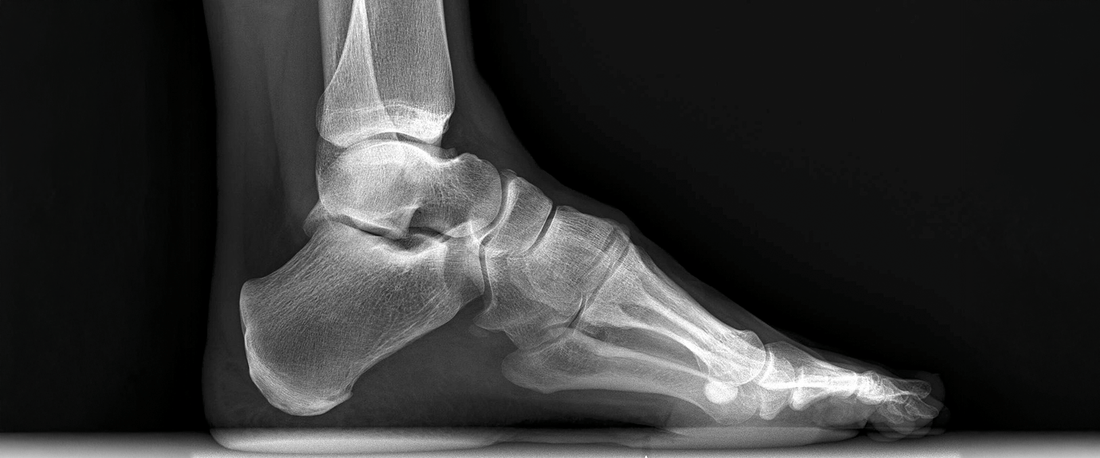

A high arch, also known as pes cavus, is a condition where the arch of the foot is higher than normal. Unlike flat feet, which lack arch support, high-arched feet don’t absorb shock as efficiently, putting extra pressure on the heel and ball of the foot.